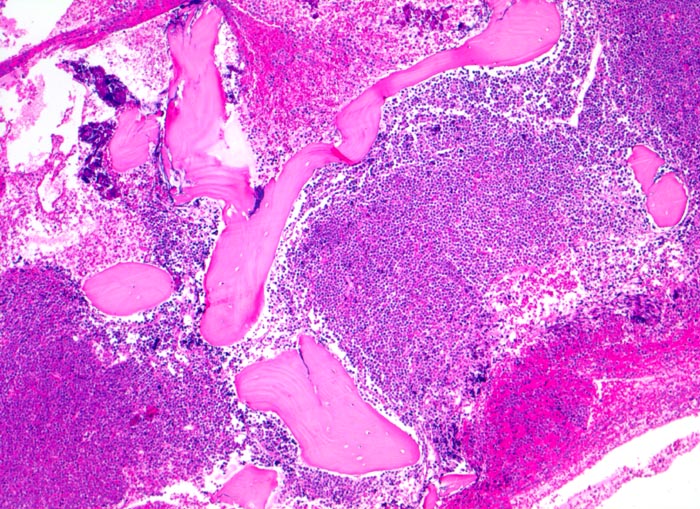

Morphologische Merkmale:

• Partielle Verdrängung des Fettmarks durch monomorphen Blastenrasen (Zellularität ca. 80%).

• Verdrängung der Myelo-, Erythro- und Megakaryopoese.

• Mittelgrosse Lymphoblasten mit wenig Zytoplasma.

• Kerne mässig polymorph, oval, teils mit Kerneinkerbungen. Feine Nukleolen. Lockeres Chromatin.

• Zahlreiche Mitosen.